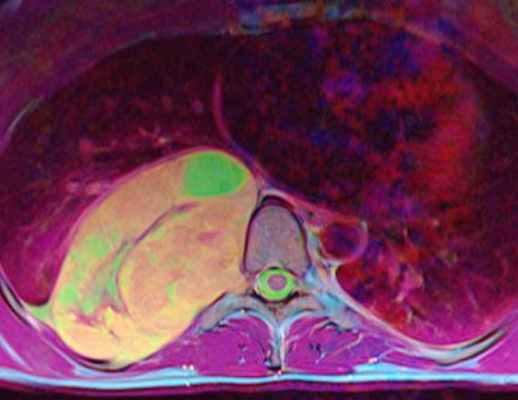

МРТ опухолей спинного мозга

МРТ позвоночника. Аксиальная Т2-взвешенная МРТ грудного отдела. Невринома по типу “песочных часов”. Цветовая обработка изображения.

При МРТ позвоночника могут быть выявлены не только дегенеративные заболевания и грыжи дисков, но и опухоли. Экстрадуральные опухоли, в основном метастазы в позвонки, рассматриваются нами в специальной статье. Интрадуральные опухоли могут быть экстрамедуллярными (внутри позвоночного канала, но вне спинного мозга) и интрамедуллярными (собственно спинного мозга). И те и другие могут проявляться миелопатическим синдромом. МРТ в СПб спинного мозга осуществляется одновременно с МРТ позвоночника по стандартным программам, с добавлением МРТ с контрастированием. Стойкое подозрение на опухоль мозга позволяет исследовать область прицельно. На открытом МРТ срезы чуть толще, однако, обычно это не сказывается на качестве диагностики. МРТ СПб позволяет выбирать место выполнения МРТ, мы рекомендуем Вам обследоваться у нас, так как имеем большой опыт МРТ позвоночника в нейрохирургии.